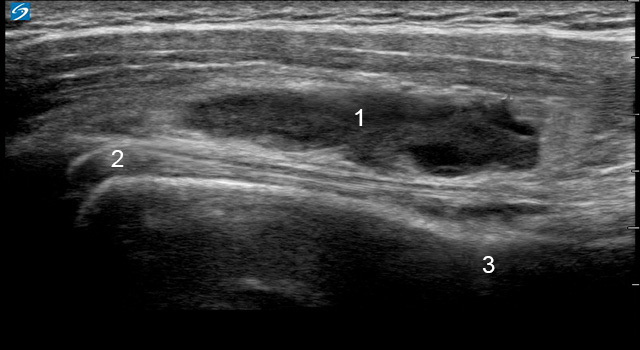

Imagen de señal «en forma de gota» de bolsa subacromial del hombro

1. Bolsa distendida anterior

2. Tendón del bíceps (TB)

3. Cuello SX anterior